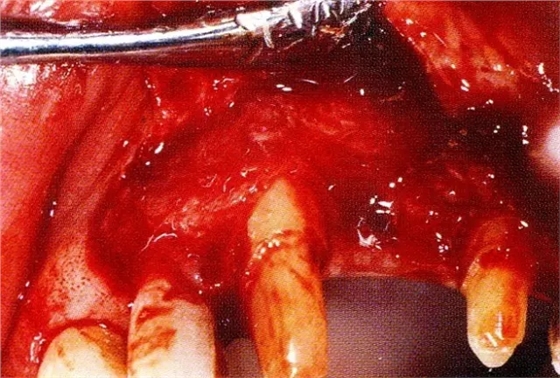

▲圖7-3將posterior interproximal類型的非吸收性覆膜修整后進(jìn)行垂直懸吊縫合做固定。垂直懸吊縫合后,確定覆膜是否會(huì)動(dòng)搖,再將齦瓣與之緊密縫合。

▲圖7-4術(shù)后1年2個(gè)月再翻開看的情況。與圖7-1的骨缺損狀態(tài)相比可知形成了臨床性骨再生。